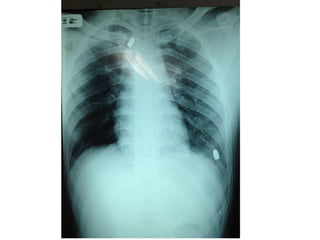

หญิงไทย 28 ถูกแฟนยิง แล้วแฟนนำาส่งโรงพยาบาลใน 20 นาที

ที่ห้องฉุกเฉิน BP 0, PR 0, RR เฮือก

• Secondary survey

HEENT : no open wound

Chest : equal breath sound , heart normal

s1s2 , no murmur

Abdomen : voluntary guarding

PR : blood

• Adjuncts to secondary survey

- Esophagogram

- CT chest and whole abdomen c IV

contrast